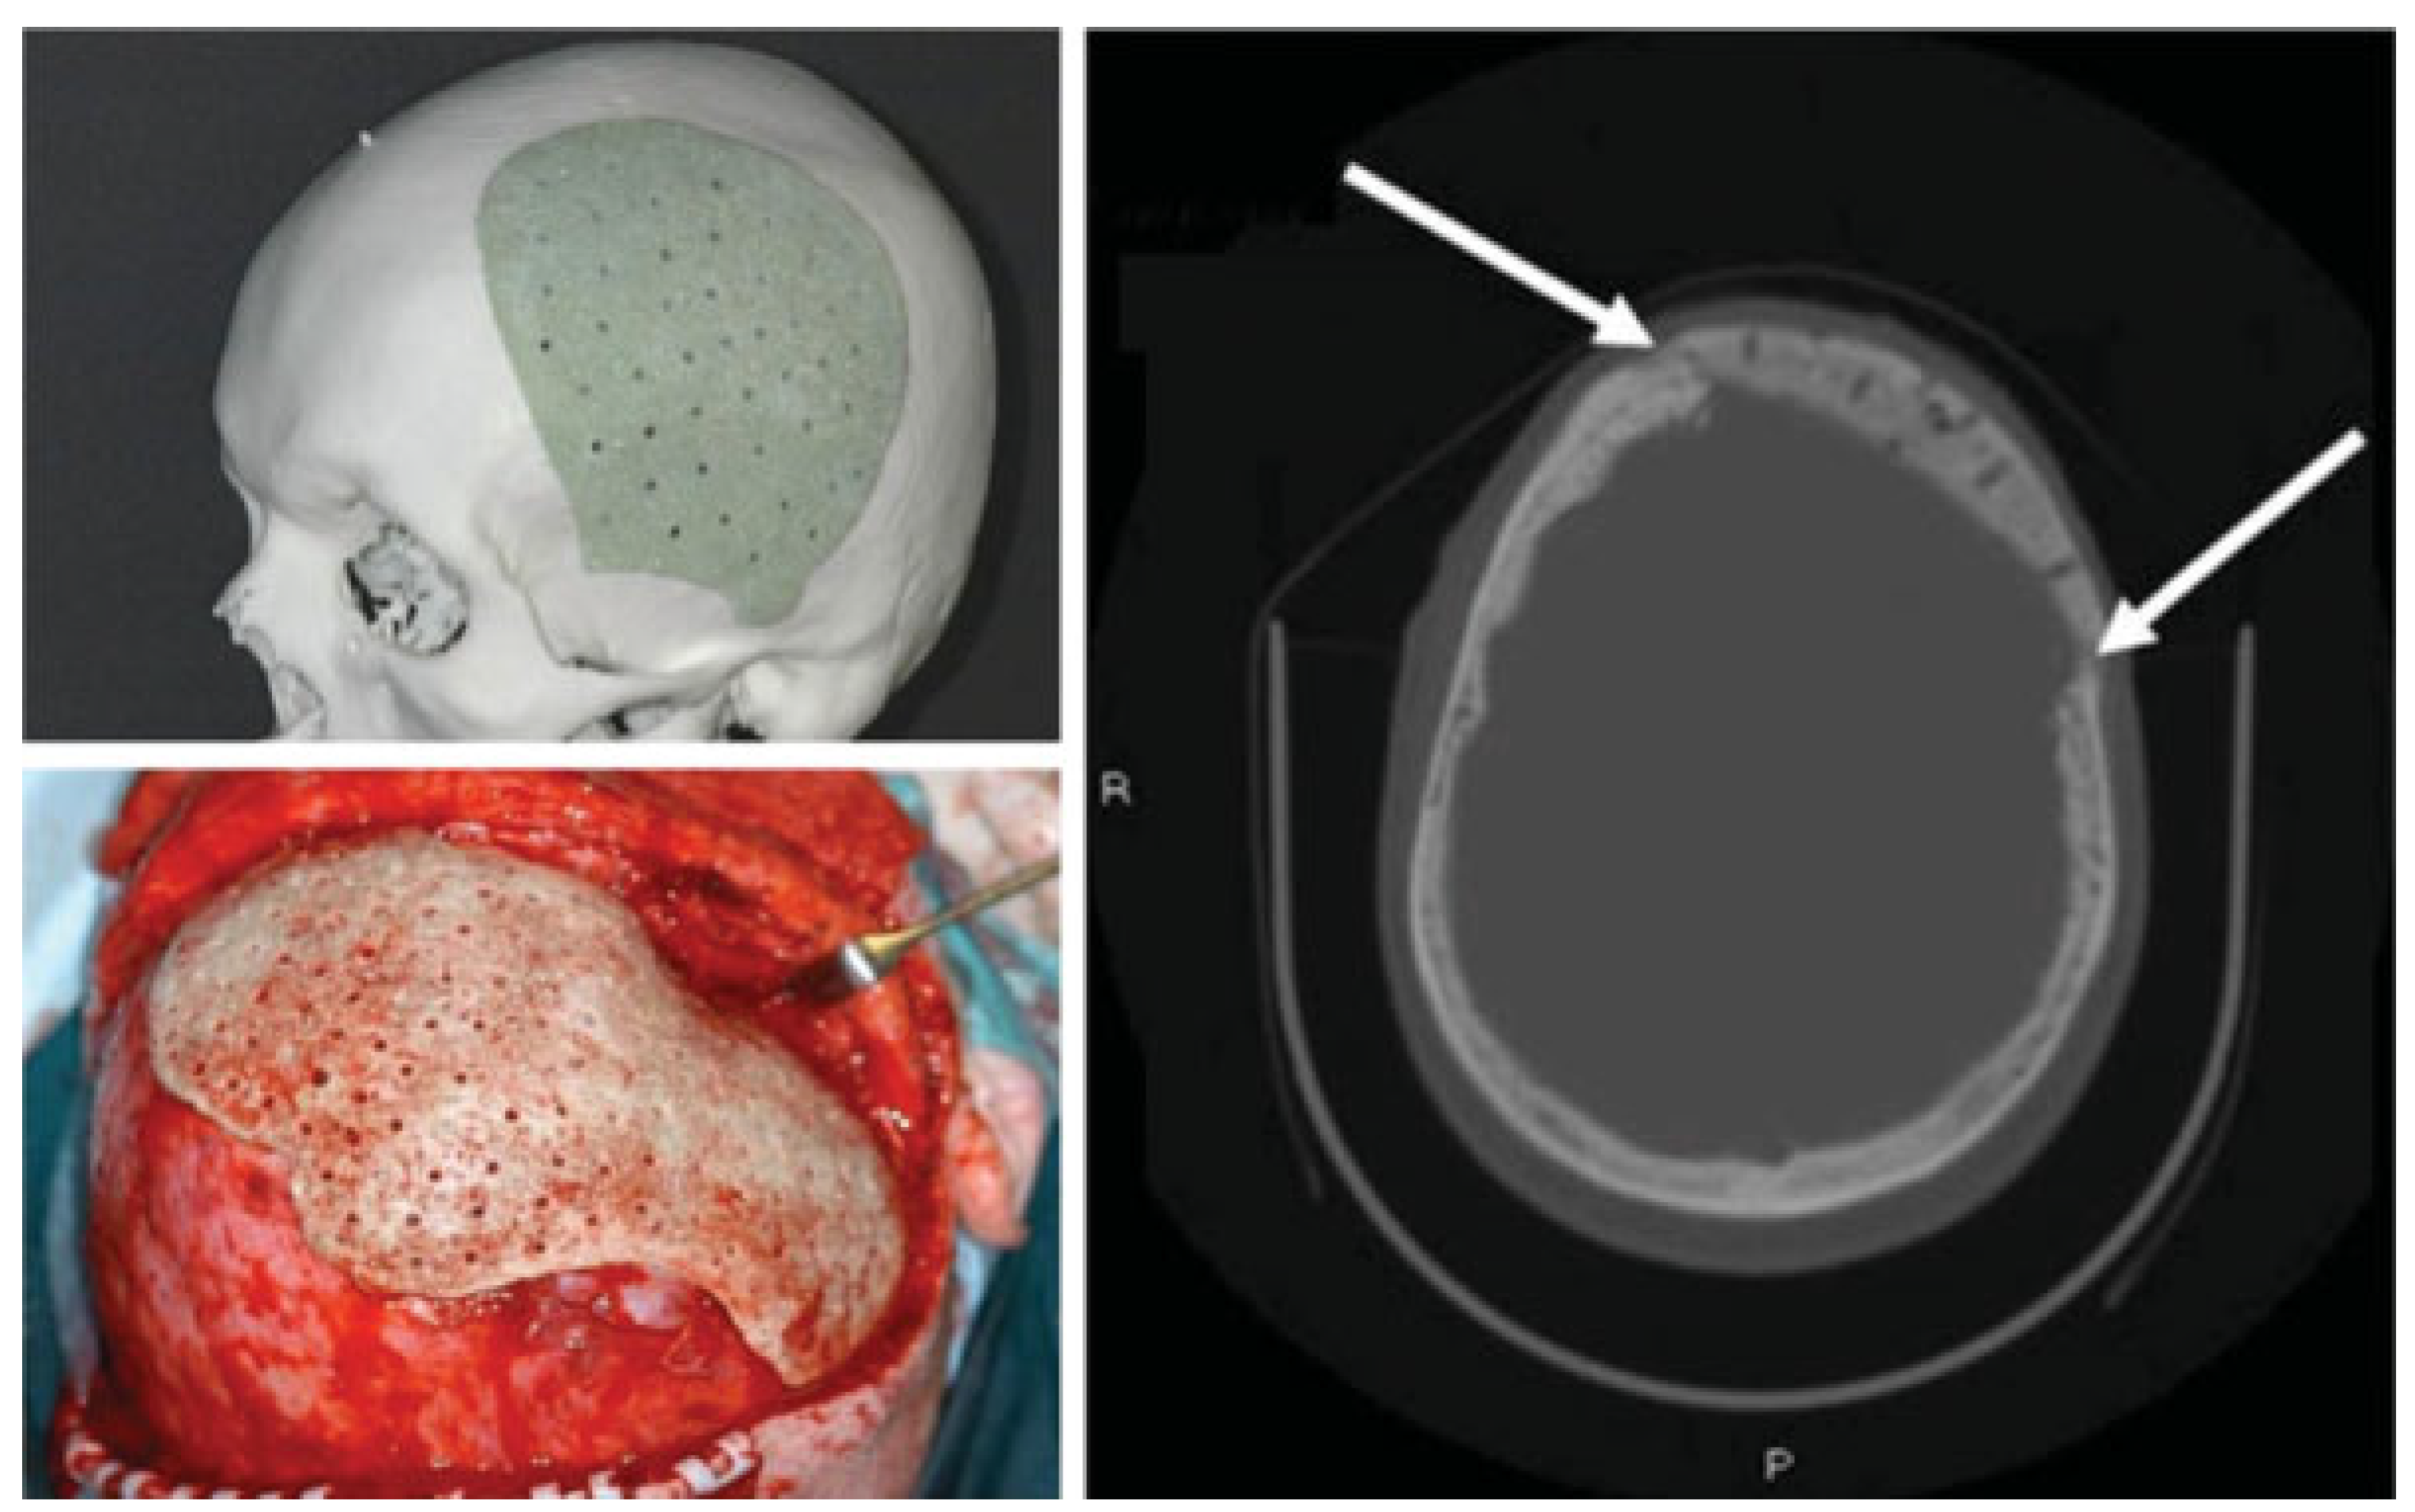

:Calvarial Defects Reconstruction